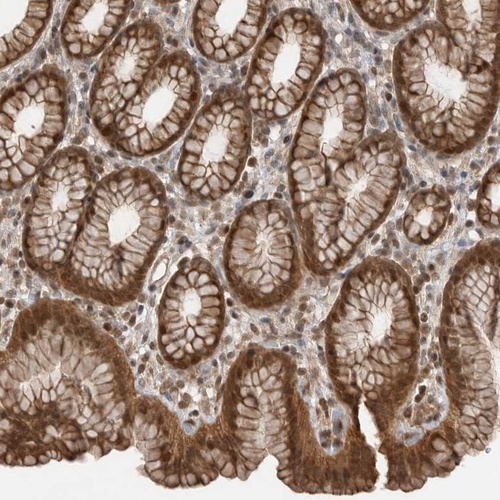

Immunohistochemical staining of human stomach shows strong cytoplasmic and nuclear positivity in glandular cells.